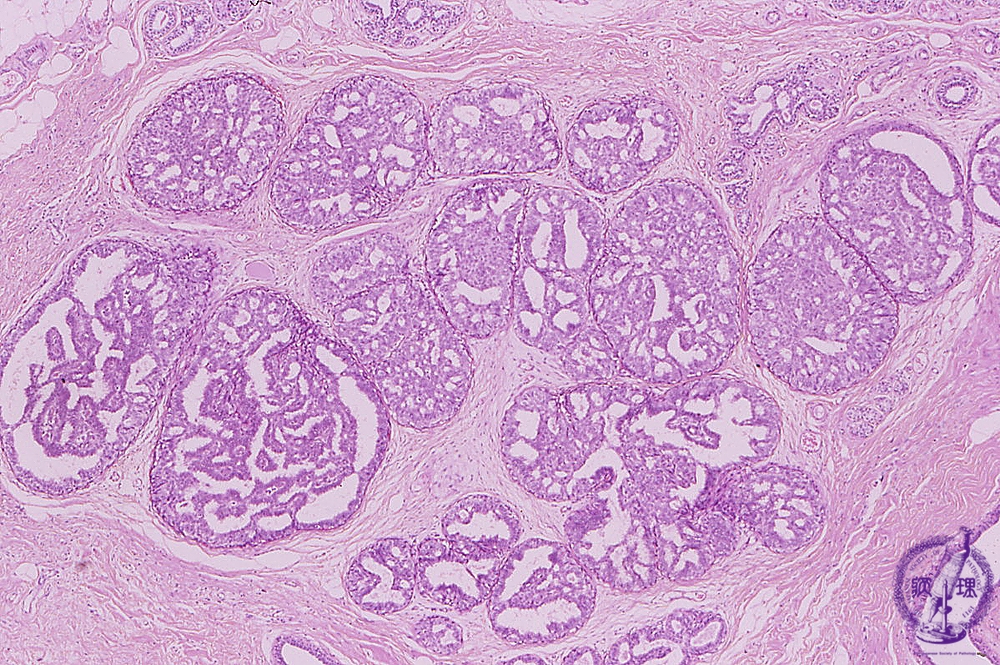

Microscopic image(HE stain, low power view):Ductal hyperplasia. Proliferating epithelium filled peripheral ducts. The differential diagnosis from carcinoma can be difficult, especially when the biphasic patterns are unclear.